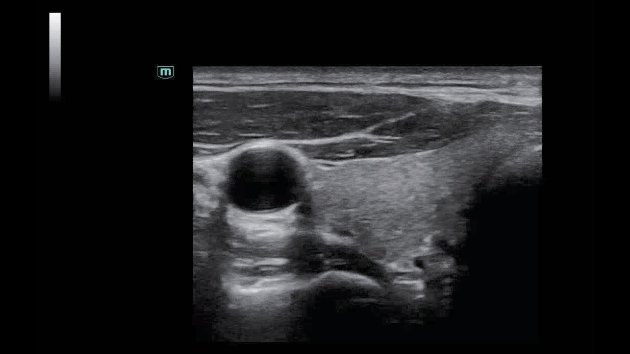

A linha Consona apresenta solu??es inovadoras e eficientes que o ajudam a realizar diagnÃģsticos em diversos tipos de pacientes.

N?o importa se sua rotina ÃĐ em hospitais, clÃnicas ou se vocÊ estÃĄ aprimorando habilidades em Imagem Geral, SaÚde da Mulher ou na ÃĄrea Cardiovascular; vocÊ encontrarÃĄ ferramentas altamente poderosas disponÃveis para manter-se na vanguarda.

Solu??es abrangentes de imagens com tecnologia ZST+

A plataforma ZST+ ÃĐ uma inova??o extraordinÃĄria, representando a evolu??o do ultrassom. Transformando as mÃĐtricas de ultrassom: da forma??o convencional do feixe ao processamento baseado em dados de canais. Supera a limita??o de compensa??o tradicional entre resolu??o espacial, resolu??o temporal e uniformidade de tecido, oferecendo qualidade de imagem excepcional para solu??es de imagem infinitas com melhorias inigualÃĄveis.